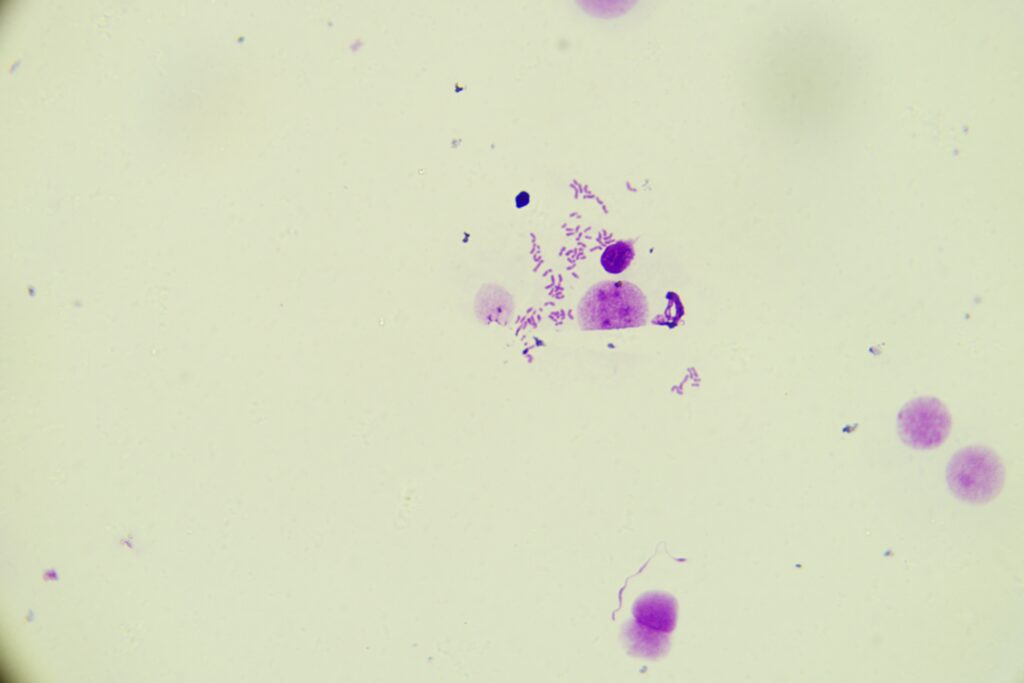

Chromosomy ludzkie XY

Chromosomy ludzkie XY